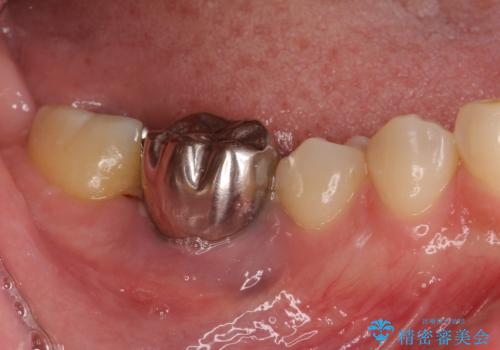

そのため右下の奥歯に強い負担が生じていて、むし歯が大きかったこともあり、抜歯が必要な状態でした。

また、右下の抜歯が必要な奥歯は、矯正治療の途中でインプラントを埋入し、矯正治療後に上顎と合わせて補綴治療を行うこととしました。